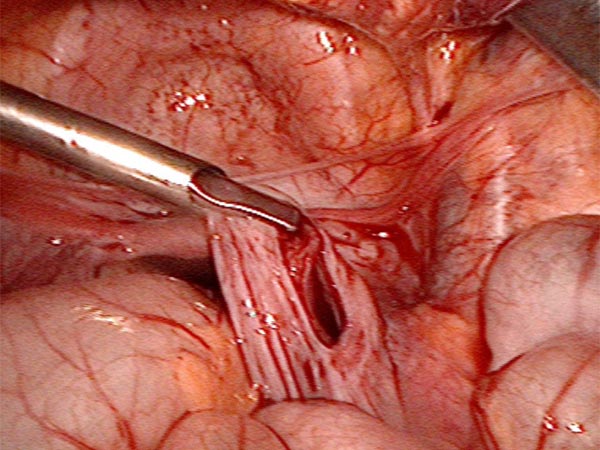

Das Peritoneum zur Bauchhinterwand wird eröffnet und alle Zysten schrittweise aus der Umgebung ausgelöst und entfernt.